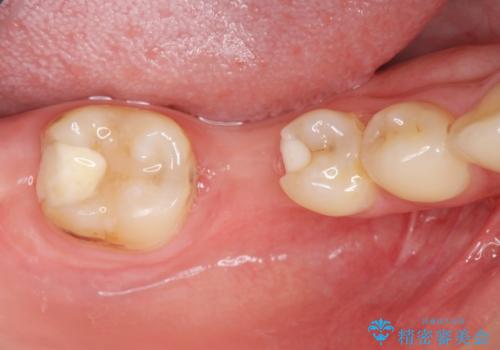

- 上下1本づつの歯を失い、噛めないことの改善を求めて来院されました。

保存可能な歯の虫歯・根管治療を行い、喪失した部分はインプラントを埋入、オールセラミックジルコニアクラウンを製作し審美的に仕上げていきます。

今回下顎の欠損部位はブリッジも検討されましたが、並行性の観点から最後方臼歯の神経を取るリスクを抑えるためインプラント治療を選択しました。